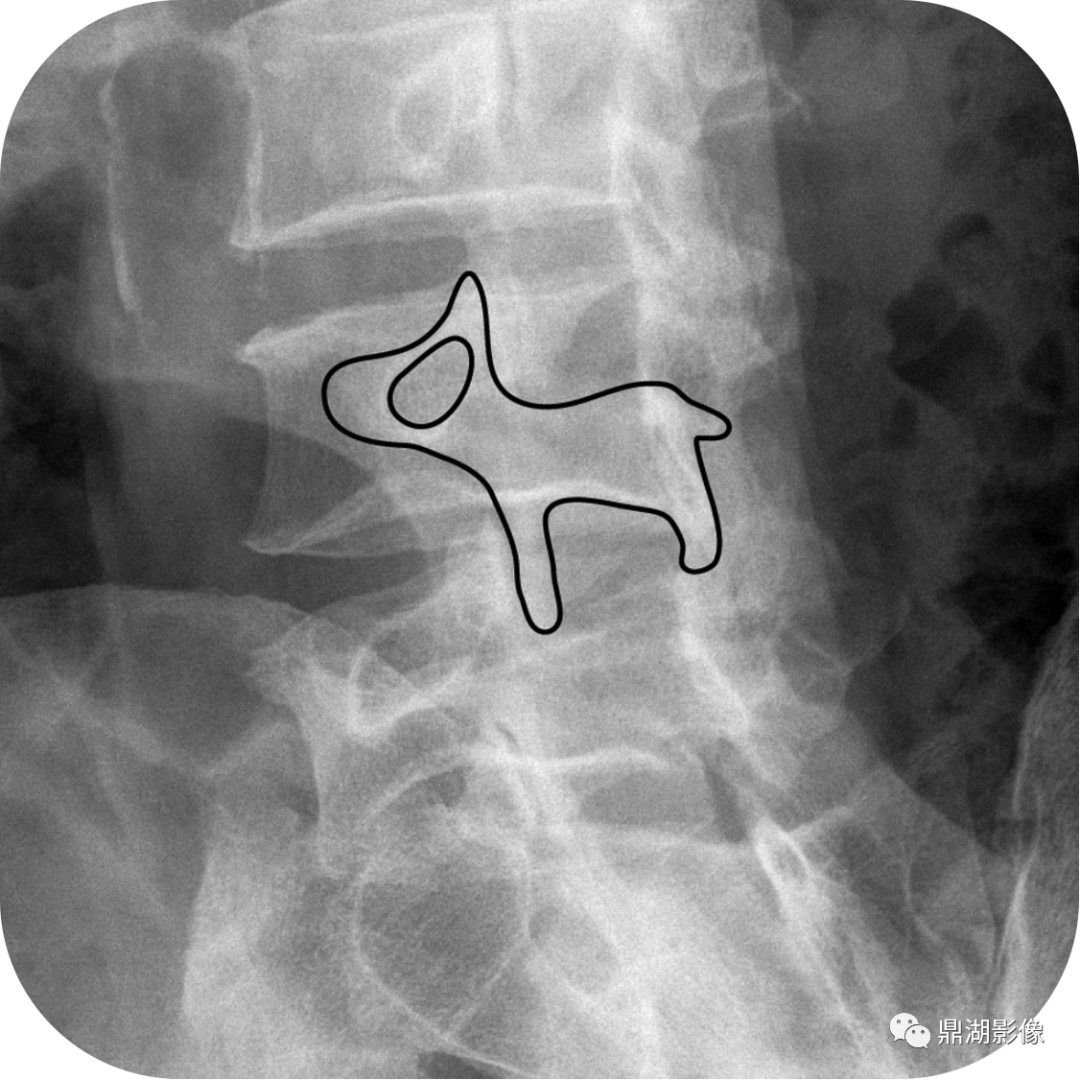

在腰椎双斜位上,正常的腰椎附件结构形似苏格兰犬外观,横突为鼻子,椎弓根形成眼睛,下关节面为前腿,上关节面为耳朵,和椎弓狭部相当于狗的颈部。

正常腰椎双斜位X线

腰椎斜位,附件结构形似苏格兰犬外观

斯科蒂犬